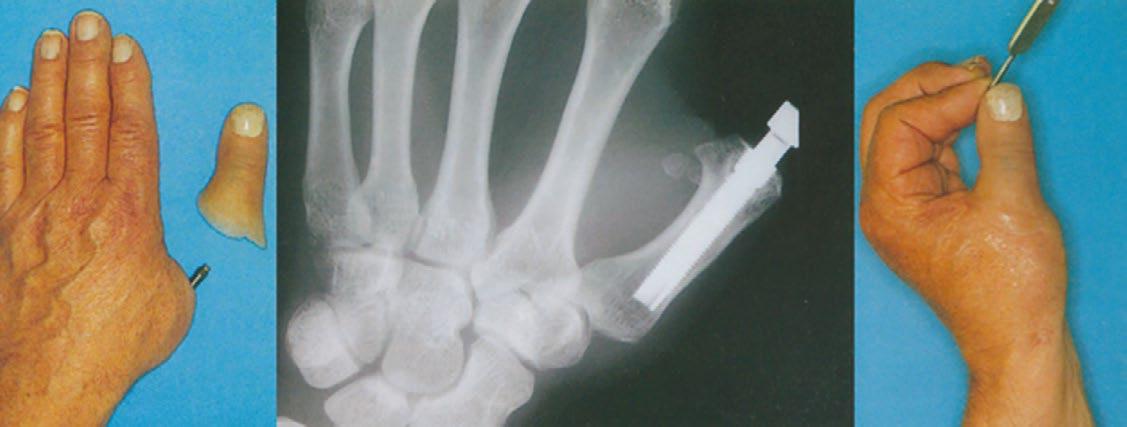

1. Hagert, Brånemark y col. en la Scandinavian Journal of Plastic and Reconstructive Surgery presentaron un caso de artroplastia de la articulación metacarpofalángica del pulgar izquierdo utilizando un implante osteointegrado. Gracias a ello, el paciente recuperó la función de pinza con la mano. (Figura 2)